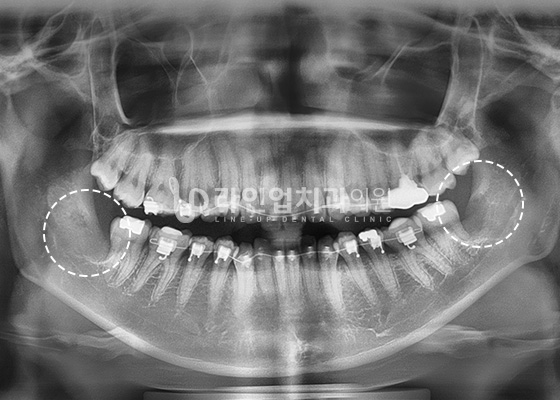

치료전 Before

치료후 After